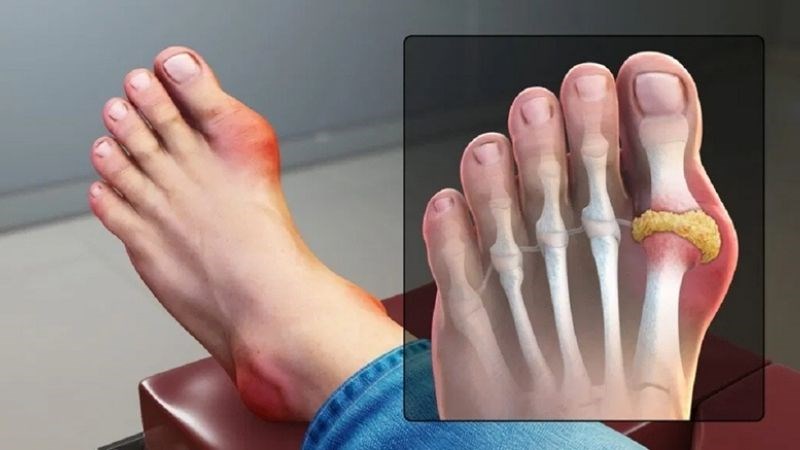

Bệnh gout (gút)

Gout là bệnh lý xảy ra do sự lắng đọng và tích tụ axit uric trong các khớp. Khi nồng độ axit uric tăng cao, các tinh thể urat có thể lắng đọng trong các khớp, gây ra tình trạng viêm và đau dữ dội. Triệu chứng đầu tiên người bệnh Gout có thể nhận thấy là tình trạng sưng đau ở ngón chân cái. Ngoài ra, tình trạng viêm đau khớp còn xảy ra ở các vị trí như mắt cá chân, đầu gối, cổ tay và khuỷu tay.

Theo tiến triển của bệnh, nếu không được điều trị hiệu quả có thể dẫn tới xuất hiện cấu trúc lắng đọng tại các vị trí khớp xương và phần mềm quanh khớp, hay còn gọi là các hạt tophi gây khó khăn trong việc di chuyển.

Gout là bệnh lý xảy ra do sự lắng đọng và tích tụ axit uric